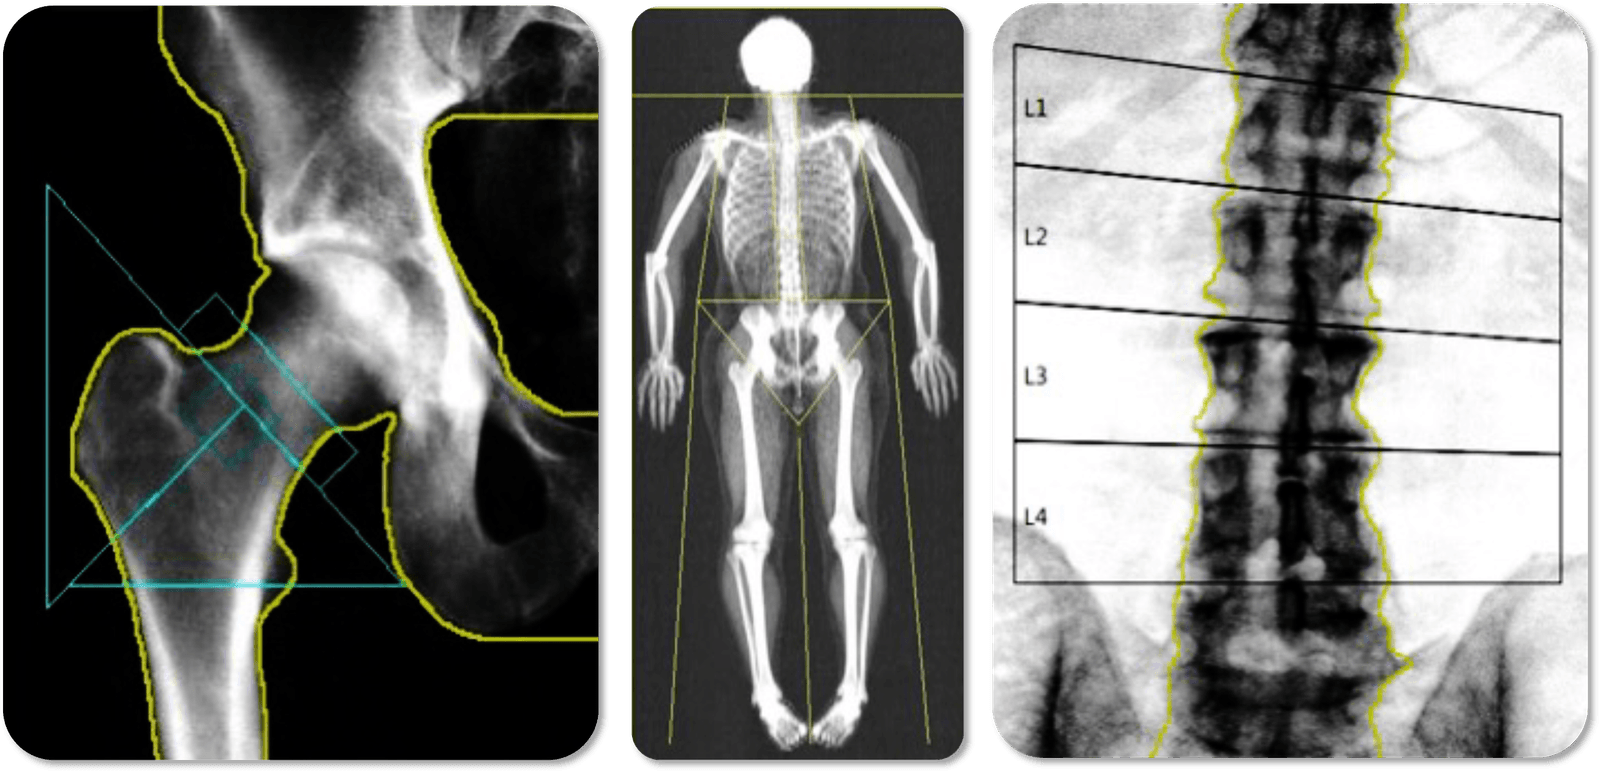

DXA

Understand body composition and bone health through a standardized and centralized reporting service, ensuring quality assurance and reliable data insights encapsulated within a configurable and customizable reporting structure.

• Lean mass

• Fat mass

• Total mass

• Percentage body fat

• Bone mineral density T-scores